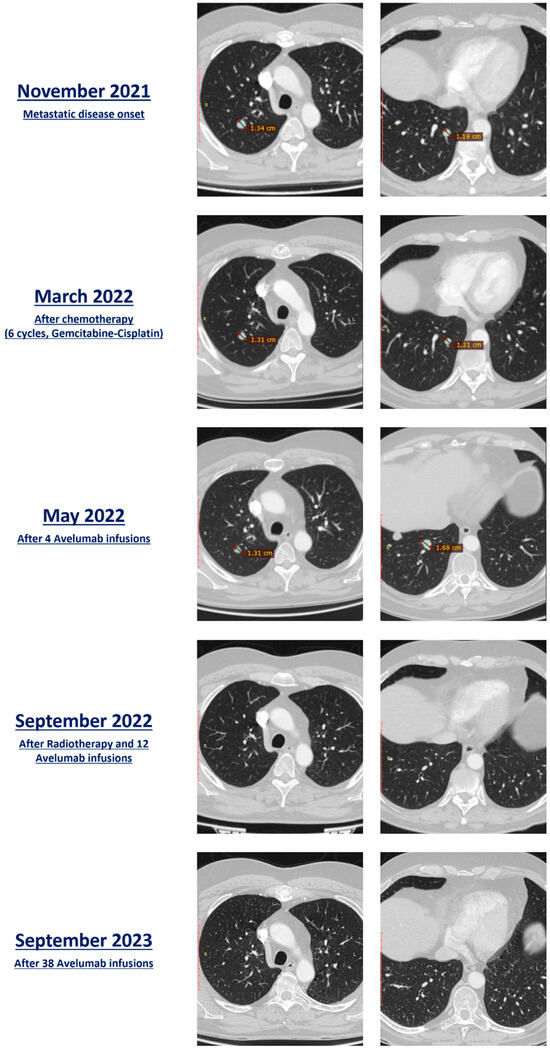

2. Case-Based Research